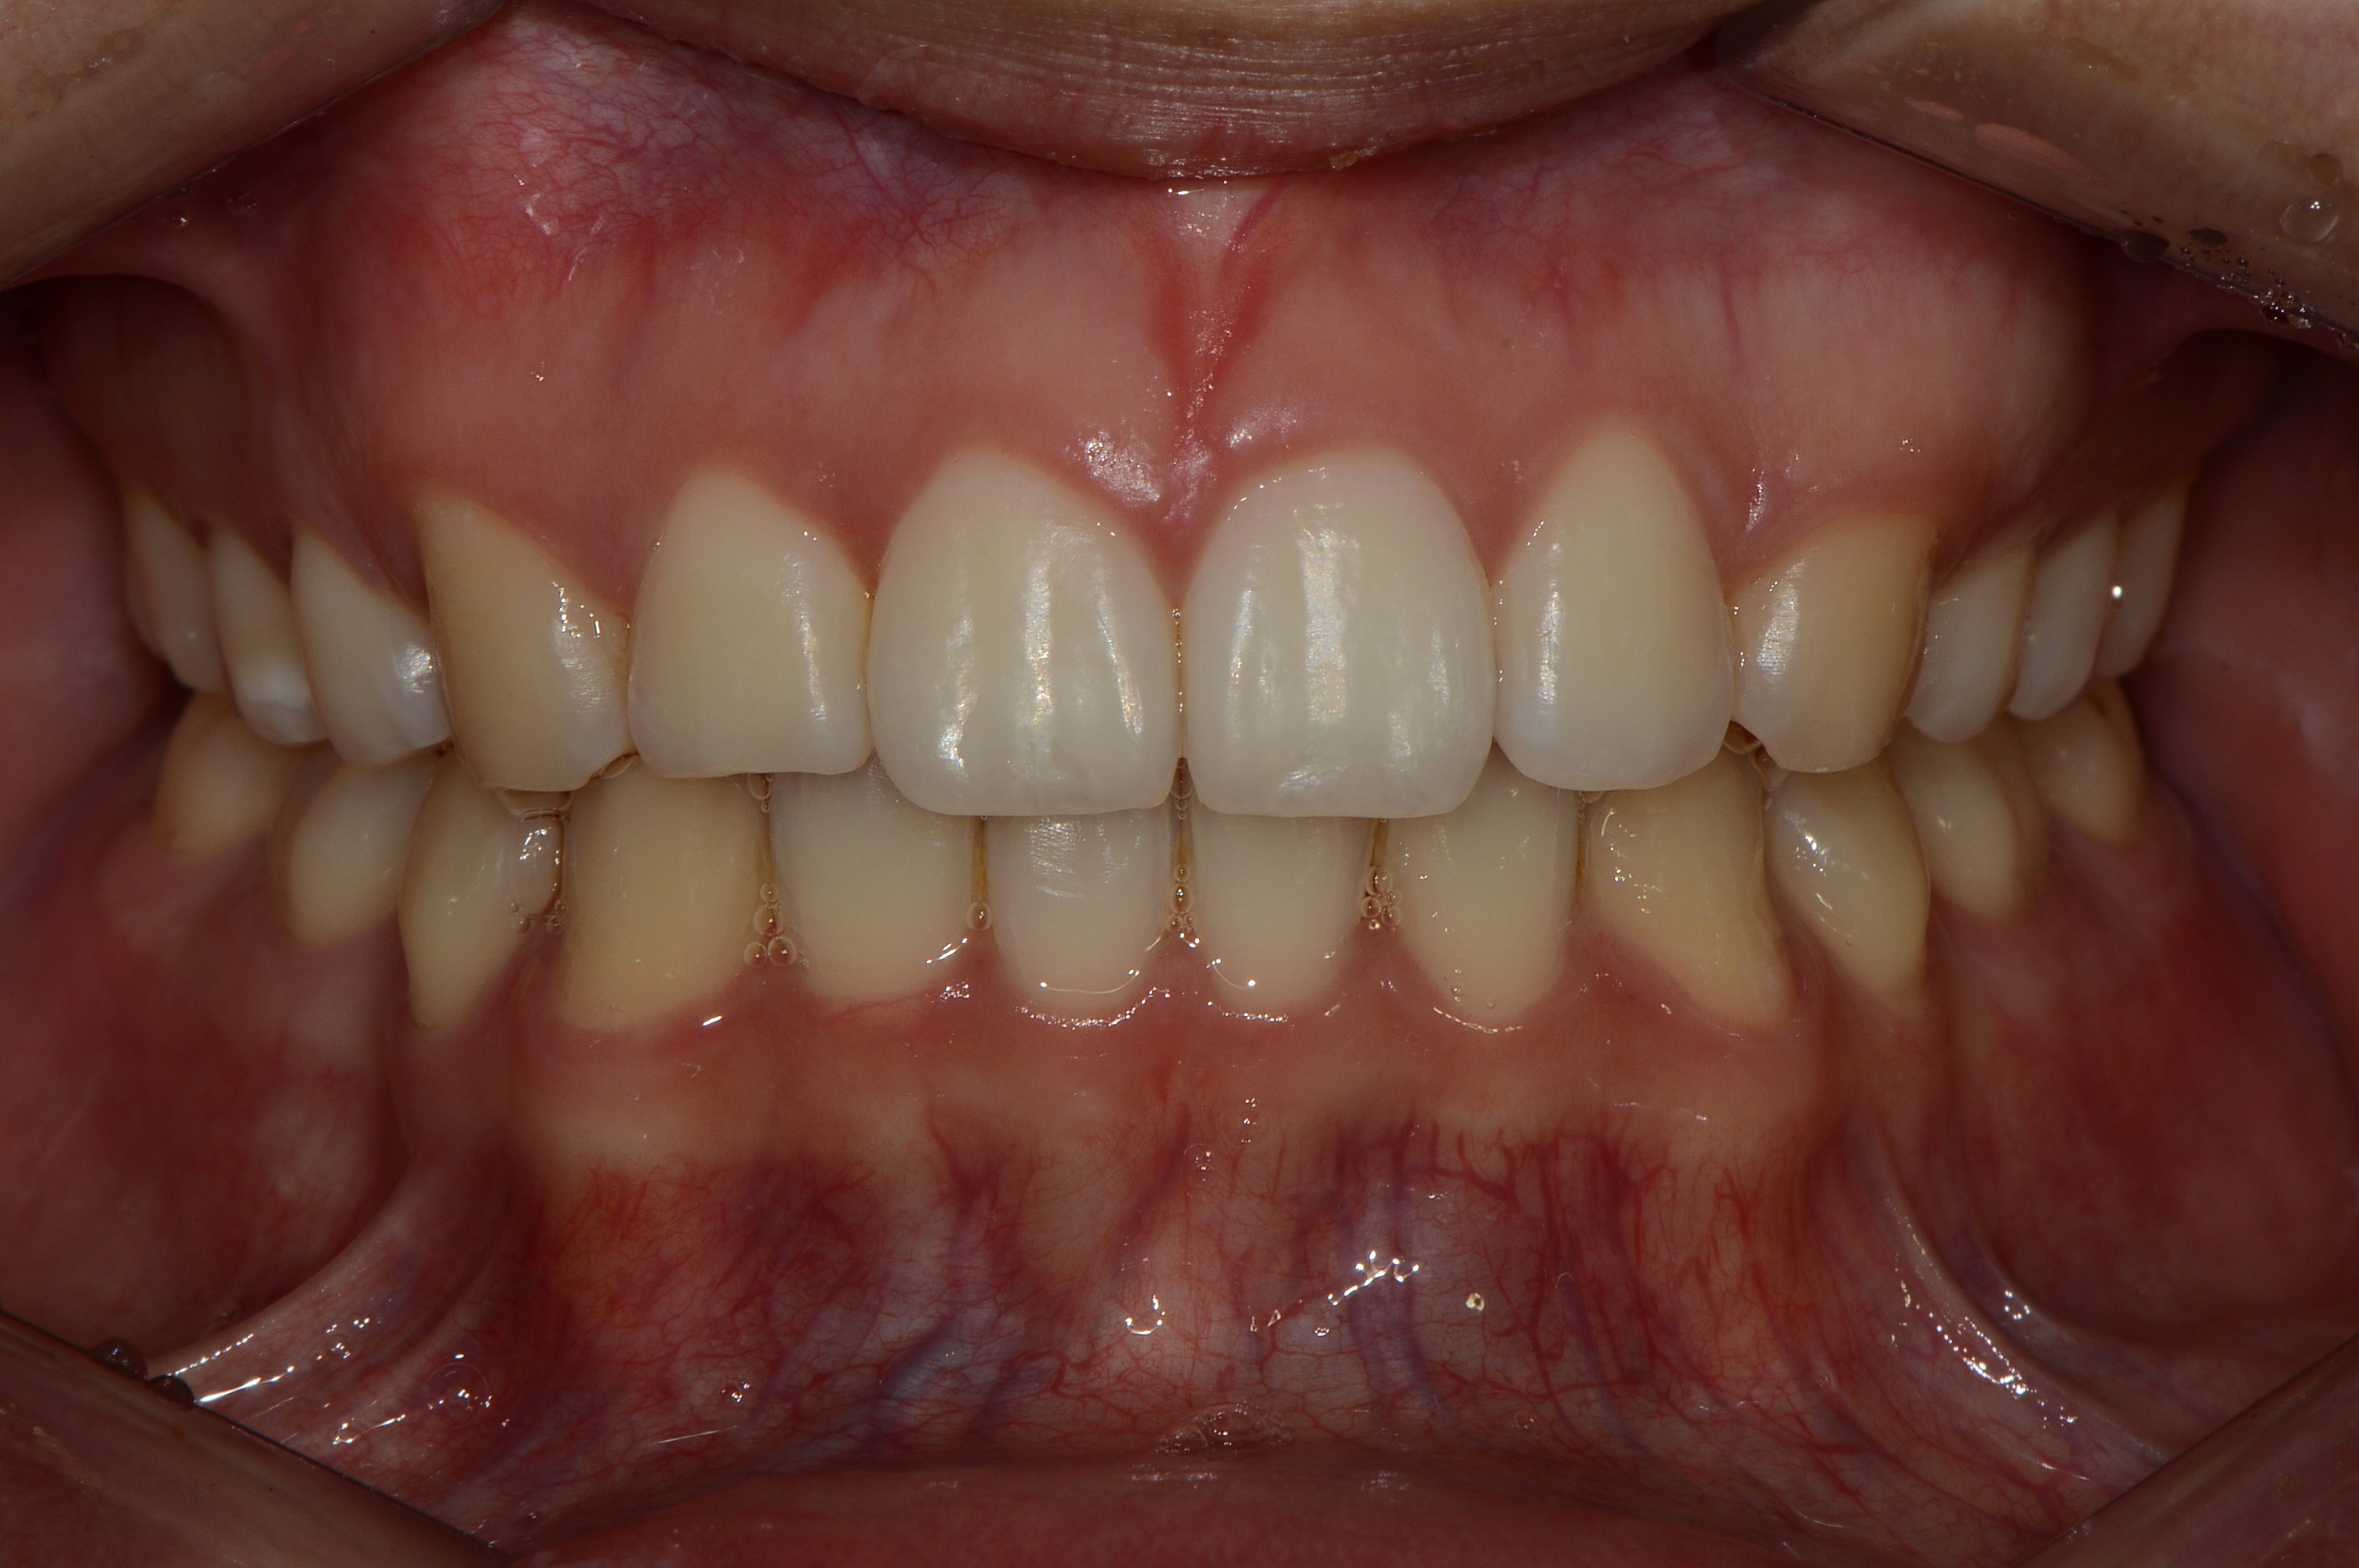

치료 후 사진입니다.